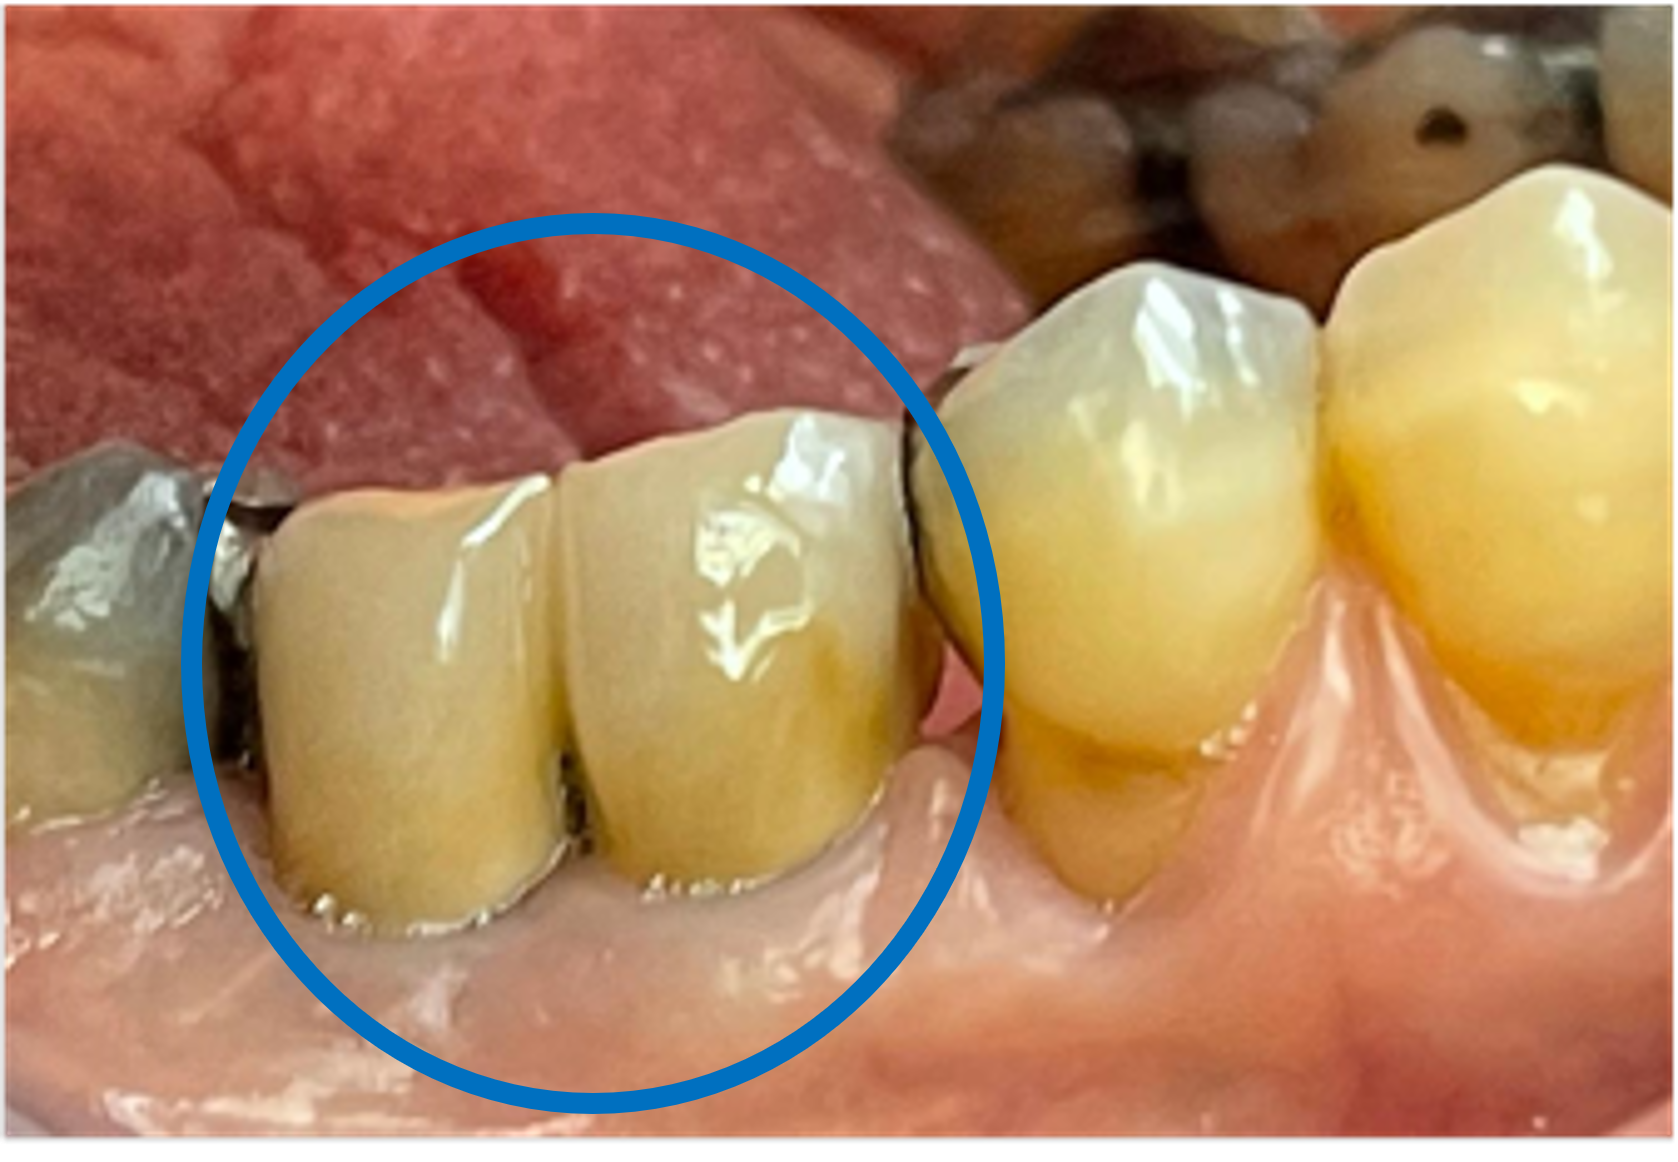

After

21 months since bone

grafting and after restoration

Bone Repair Results

Very satisfactory healing process. No complications. Full bone height preserved.

No Bone Loss observed, CoreBone granules hardly seen - indicating full bone regeneration.

Implants process very successful as well as high patient satisfaction.